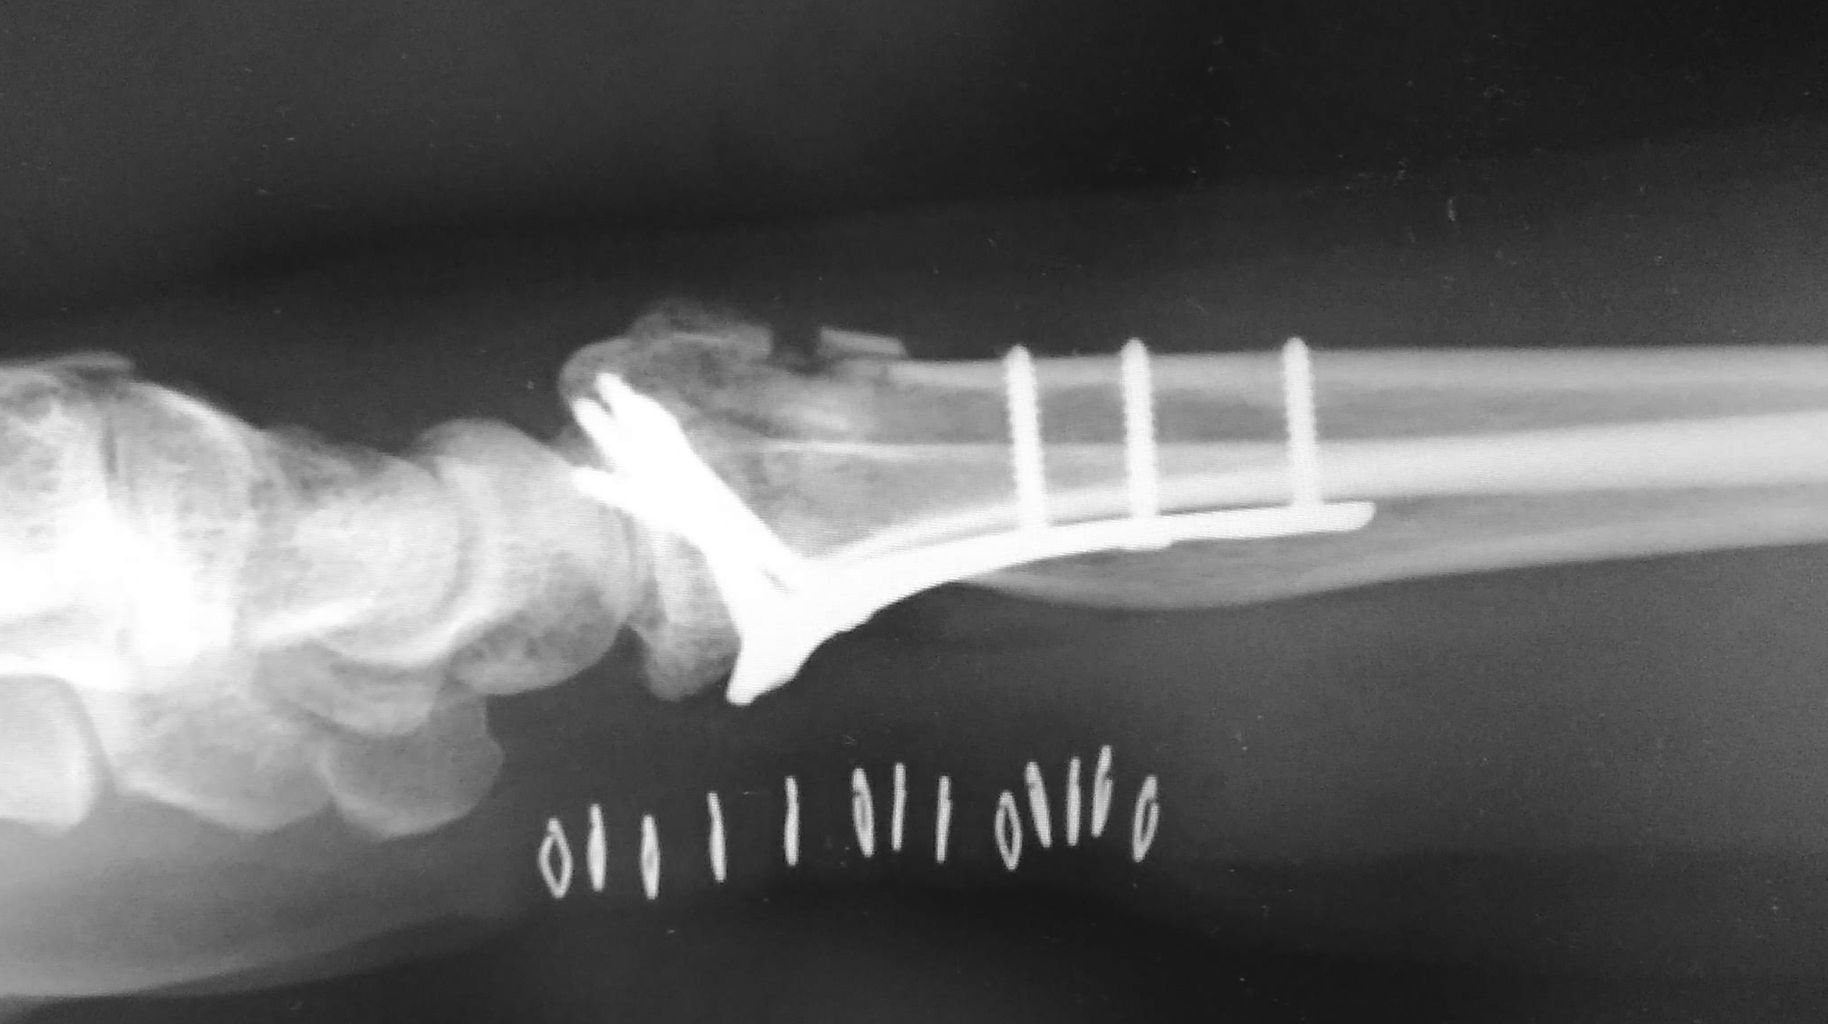

下の画像のように、かなり厳しい転位のある症例でした。

今回は、末梢側骨片の海綿骨が圧壊しており、整復するとかなりの骨欠損が生じる可能性があります。このような症例では、骨移植するべきなのでしょうか?

上記が術後の画像なのですが、少なくとも単純X線像では骨欠損はあきらかではありません。まぁ、絶対に骨欠損は存在しているはずなのですが、画像的には気にならないです。